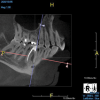

(11.) A pathosis apical to the maxillary central incisors was initially not diagnosed after evaluating the periapical film; however, the CBCT image revealed its presence. Only using the CBCT image could it be determined that the lesion was not odontogenic in origin and that it did not involve the nasopalatine foramen. This diagnosis was supported by a referral to an oral and maxillofacial radiologist.

Figure 11

(12.) A pathosis apical to the maxillary central incisors was initially not diagnosed after evaluating the periapical film; however, the CBCT image revealed its presence. Only using the CBCT image could it be determined that the lesion was not odontogenic in origin and that it did not involve the nasopalatine foramen. This diagnosis was supported by a referral to an oral and maxillofacial radiologist.

Figure 12

Are most or all dentists qualified to read CBCT images? Although the technology can be intimidating to clinicians who are not experienced in its use, the truth of the matter is that it is easier to identify structures and pathoses in CBCT images than in any 2D radiograph. This is made clear by the ability of patients to see and understand the images presented to them without receiving any formal training whatsoever. Because all dentists are trained in radiology, they can easily read a radiographic image created by a cone beam. The real issue for clinicians involves mastery of the software that their particular CBCT unit uses so that they can manipulate the images and best visualize the area in question.9 To this end, the education and training provided by the manufacturers of CBCT units can be very helpful to clinicians before they are able to gain experience through multiple evaluations of images (Figure 11 and Figure 12).

Dentists who become experienced in evaluating CBCT images become more advanced in their knowledge of anatomy as well as their familiarity with variations in normal structures. As they experience more findings, they also learn to better differentiate between normal and pathological scenarios and recognize pathoses in greater depth and detail. If dentists see something that they are not familiar with or comfortable identifying, they can refer the patient to an oral and maxillofacial radiologist.